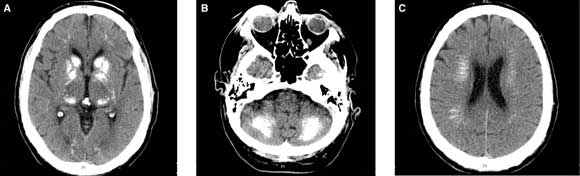

A 66-year-old man presented with a 12-month history of progressive gait disturbance with cerebellar ataxia and extrapyramidal features. Computed tomography of the head showed calcification of the basal ganglia and dentate nuclei of the cerebellum, and periventricular calcification (Box).